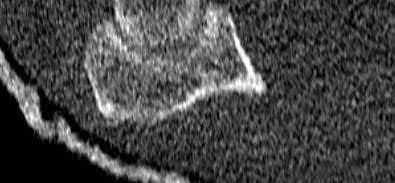

What physical exam finding is most likely to be found in association with the injury shown in Figures A and B?

The x-ray shows a fracture of the anteromedial facet of the coronoid with an intact radial head. Large anteromedial facet fractures are associated with varus posteromedial rotatory instability.

The anteromedial facet of the coronoid provides support to the medial elbow against varus stress. Varus and posteromedial force applied to the elbow results in disruption of the lateral collateral ligament (LCL) from its proximal origin. The coronoid is fractured as it is forced against the medial trochlea.

Coronoid fractures of significant size involving the sublime tubercle (insertion of medial collateral ligament) result in varus instability.

Figure A is an AP view of an elbow with an anteromedial facet of the coronoid fractured. The lateral joint space is widened due to injury to the LCL. The medial joint space is narrowed and collapsed. A lateral view is shown in Figure

B. Illustrations A and B show AP and lateral views of a coronoid fracture fixed with buttress plating. The LCL origin was fixed with a suture anchor. Illustration C shows the O'Driscoll classification of coronoid fractures. Illustration D lists injury patterns that suggest posteromedial versus posterolateral rotatory instability.